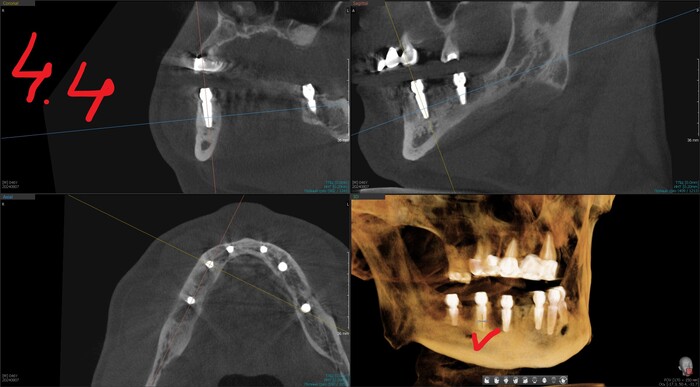

Результат такой - торки получены эталонные везде, кроме двух крайних имплантатов слева (3.4 и 3.6). Но не страшно, сверху зубов-антогонистов нет, нагрузки на протез не будет серьёзной. Да и "всё на 6" прощает подобное.

Позиция 4.6

Имплантолог видит, сколько мм можно докрутить безопасно для структур челюсти (нервов, сосудов). Делает дело.